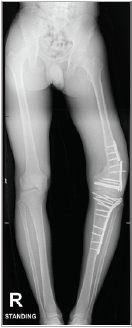

Figure 4:Full length antero- posterior plain radiograph at ten weeks post operative shows compete correction of the angular deformity

He underwent removal of implant, corrective osteotomy, left Illizarov external fixation and gradual deformity correction (Figure 3). Intra- operatively there was no local signs of infection to the distal femur and intra- operative cultures came back nil of growth/ organism. At ten weeks post-operative the deformity was corrected (Figure 4).